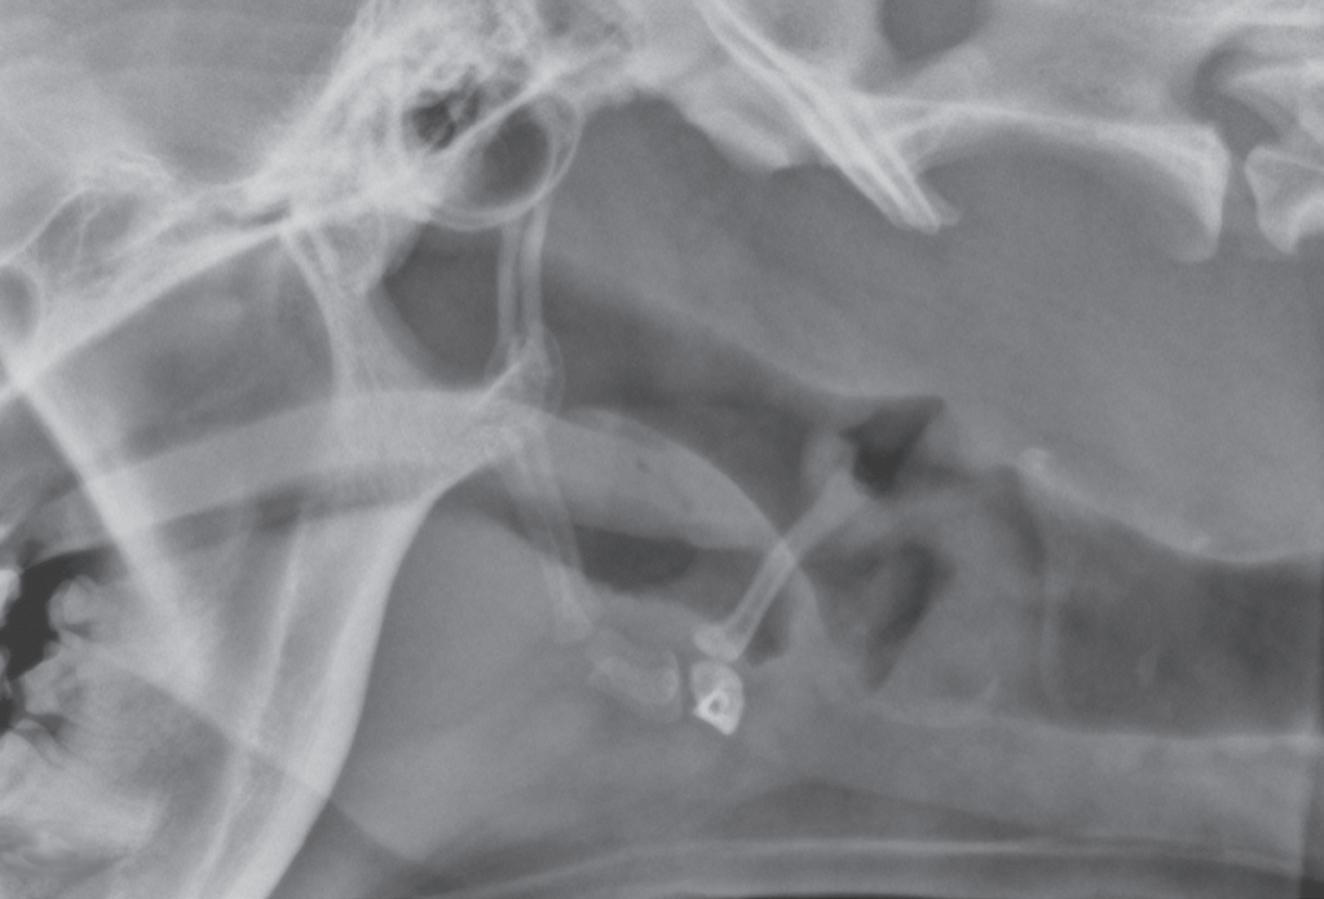

Making the same standard orthogonal views of every body part is very important. Looking at the same radiographic projections and orientations repeatedly makes it easier to recognize abnormal from normal. On the other hand, when an object or body region is radiographed using an unconventional point-of-entrance to point-of-exit of the x-ray beam, the image becomes less recognizable and more diffcult to interpret (Figure 1-6).

Figure 1-6. Dorsoventral (A), lateral (B), and rostrocaudal (C) radiographs of a box turtle. In A and B, which are orthogonal to each other, it is clear that the subject is a turtle. Eggs are visible in the coelom. In C, which is also an orthogonal view with respect to both A and B, it is not obvious that the subject is a turtle because this orientation is uncommon and unfamiliar. The eggs are also not visible in C.